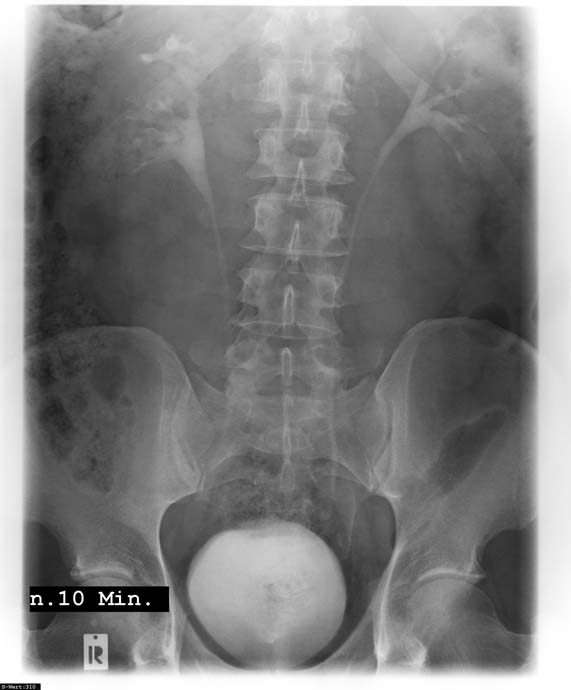

Röntgendiagnostik

Unsere Praxis betreibt eine Kooperation mit der Radiologischen Abteilung des Albertinenkrankenhauses, Hamburg.

Wie verfügen somit über eine leistungsfähige Röntgenanlage zur Erkennung krankhafter Strukturen an Nieren und ableitenden Harnwegen (z.B. Nieren- und Blasentumor, Steine im Bereich der ableitenden Harnwege, Verengungen der Harnleiter und der Harnröhre)

Es besteht außerdem die Möglichkeit zur Durchleuchtung.